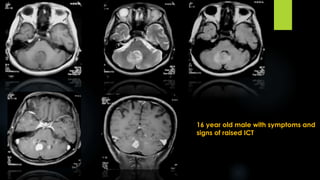

16 year old male with symptoms and

signs of raised ICT

Hemangioblastoma

 Presentation- headache, disequilibrium, dizziness

 Age- 40-60 years

 VHL associated occur in younger age group

 IMAGING FINDINGS:

 Best diagnostic clue - intraaxial posterior fossa mass with cyst, enhancing mural nodule abutting

pia

 Location - cerebellar hemisphere- 80%

Hemangioblastoma (contd.)

 CT:

low density cyst + isodense nodule

intensely enhancing nodule

Cyst wall doesn’t enhance

 MRI:

T1WI- nodule isointense to brain, cyst slightly hyperintense compared to CSF

T2WI- both nodule & cyst are hyperintense

Post contrast- intensely enhancing nodule